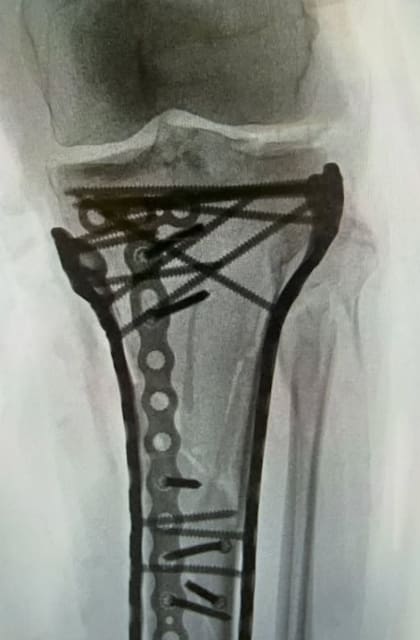

“Tuve una fractura compleja de tibia y de peroné, y la razón de su complejidad fue el síndrome compartimental. El síndrome compartimental se produce cuando un traumatismo en una zona es tan fuerte que la sangre se acumula. Básicamente, lo aplasta todo: músculos, nervios, tendones, y muere“, dijo Vonn para que sus seguidores dimensionen la magnitud del hecho. A su vez, la damnificada recibió una transfusión de sangre y varios calmantes para aplacar el dolor en la zona herida.

Con el recuerdo latente de la operación, la deportista estadounidense graficó: “Abrió ambos lados de mi pierna, la dejó respirar y me salvó de ser amputada”. Superada esta instancia de alto impacto emocional, Vonn permaneció por dos semanas en una cama de un hospital completamente inmovilizada y monitoreada por profesionales.

“Ahora me centraré en la rehabilitación y en progresar de una silla de ruedas a muletas en unas pocas semanas. Tomará alrededor de un año para que todos los huesos sanen y luego decidiré si quiero sacar todo el metal o no, y luego volver a la cirugía y finalmente arreglar mi ligamento cruzado anterior”, agregó sobre su impactante historial de lesiones que posiblemente la condicione para una recuperación definitiva de la zona dañada.